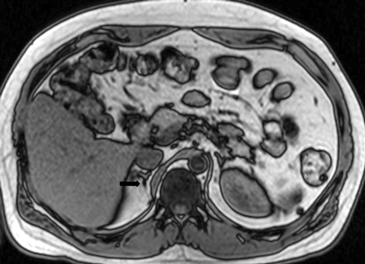

En la TC no contrastada las glándulas suprarrenales normales son homogéneas y simétricas, con una densidad muy similar a la del parénquima renal adyacente (Figura 1 a). Con un medio de contraste ev la glándula suprarrenal se opacifica en forma homogénea, similar al hígado o al bazo (Figura 1 b). Si la cantidad de tejido adiposo retroperitoneal es abundante las glándulas suprarrenales pueden aparecer enteramente rodeadas por grasa y su delimitación es más fácil (Figura 2 a); lo inverso ocurre en pacientes muy delgados con escasa grasa retroperitoneal (Figura 2 b). En RM, en secuencias ponderadas en T1 y T2 convencionales tienen una intensidad de señal homogénea, hipointensa respecto de la grasa adyacente e iso o hipointensa con respecto del parénquima hepático (Figura 3 a y b). En los cortes coronales se aprecia mejor la forma y la posición de las glándulas suprarrenales (Figura 3 c).

Figura 3. Glándula suprarrenal normal en resonancia magnética. (a) Cortes axial ponderado en T1 la señal de la glándula normal (flecha negra) es hipointensa respecto a la grasa retroperitoneal e isointensa respecto al parénquima hepático. (b) Cortes axial ponderado en T2 en que se muestra la glándula suprarrenal derecha (flecha blanca) y (c) corte coronal ponderado en T2 en que se muestra la glándula suprarrenal derecha (flecha blanca) y la glándula suprarrenal izquierda (flecha negra) con similares características de intendidad de señal. 3. Causas y prevalencia de las lesiones suprarrenales